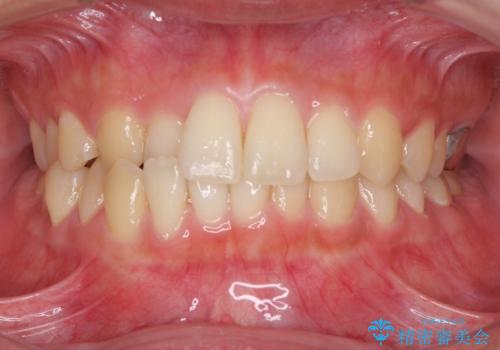

- 前歯のクロスバイトを気にして来院され患者様です。

定期的に日本には帰国するものの、日ごろは海外でお仕事をされているとのことで、インビザラインによる治療を希望されました。

トラブルが起こった時に対応ができない、来院を帰国のタイミングに合わせなければならないため治療が長期化するなど困難はありますが、ワイヤー矯正と比べると治療を進めやすいといったメリットがあるので、インビザラインにて矯正治療を行うこととしました。